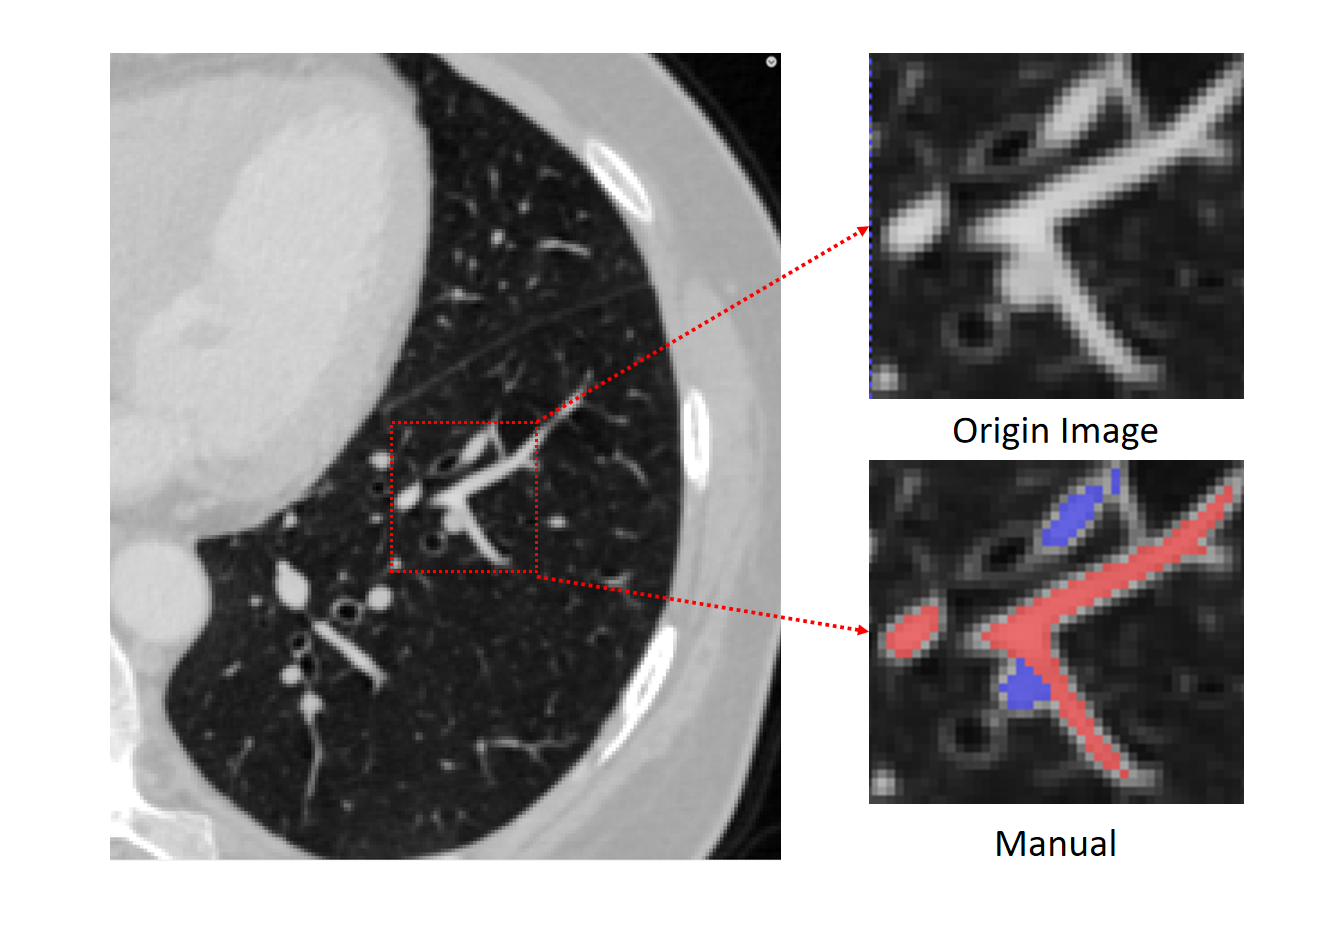

At present, the automatic separation of pulmonary arteries and veins from multislice CT is always an open problem, especially in noncontrast CT scans due to the following reasons: 1) A/V is indistinguishable by its similar intensity values in noncontrast CT images. 2) The vascular tree structure is extremely complex and dense, with arteries and veins close to each other and intertwined. 3) Artifacts, partial volume effects, and patient-specific vascular tree structural abnormalities cause difficulty of A/V segmentation. CT provides images with near-isotropic submillimeter resolution. It enables a detailed display of the pulmonary vessels. The details are shown in Fig. 1. In addition, it can be seen that it is difficult for doctors to make an accurate manual standard based on voxel levels from the original CT images.

With the development of AI-assisted medical imaging diagnostic system, many scholars have tried to propose their own pulmonary A/V separation methods in the last decade, although it is very difficult. Despite the vasculature inside the lungs is very variable, some inherent anatomical properties are usually found. One property is that arteries run along the bronchi, and the veins run in between their branches. As shown in Fig. 2, the trachea with the accompanying artery is not evident when the vessels are near the hilum of the lung. As the artery moves away from the hilum, the bronchi begin to follow the artery closely. Some methods rely on the bronchi for A/V separation. Tozaki et al.[2] used information about distances between vessel segments and bronchi to separate the arteries and veins. Y.Mekada et al.[3] classified pulmonary artery and vein from X-ray CT images according to the distance from the bronchus region to the vessel segment and the distance between the nearest inter lobar to the vessel. Similarly, Buelow et al.[4] designed a method of “arterialness” to classify each extracted vessel segment. However, these methods of A/V separation depend on the quality of airway segmentation.